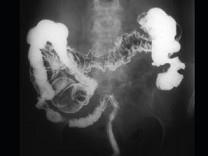

问题 男,46岁,患者低热、乏力,时有腹痛,请结合图像,选择最可能诊断()

选项 A.横结肠癌 B.横结肠淋巴瘤 C.横结肠转移瘤 D.假膜性肠炎 E.溃疡性结肠炎

答案 B